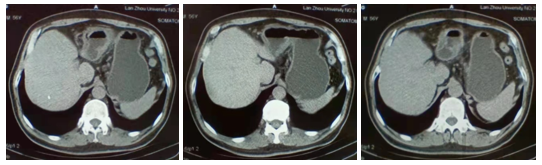

影像学检查:2021.02.20腹部CT:胃窦癌(T3/4期)幽门上下多发小淋巴结。

图1 腹部CT